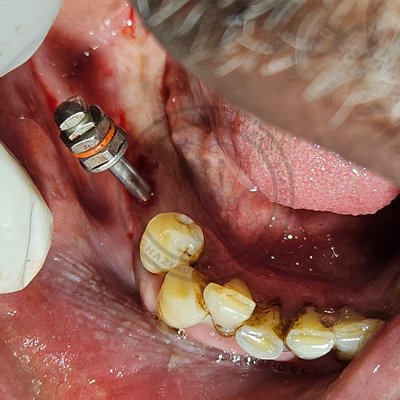

Case – 11 Baleram